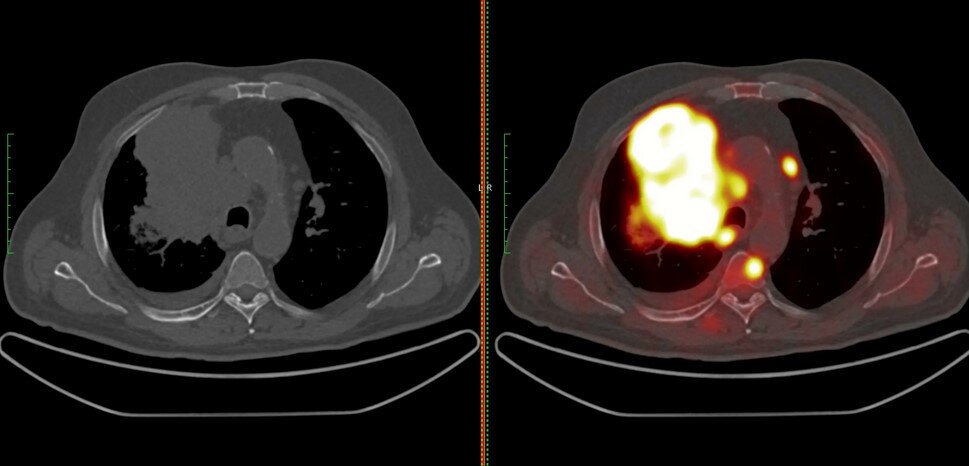

3. ПЭТ КТ

Данное обследование схоже с обычной компьютерной томографией, но оно назначается в основном для получения более детального изображения опухоли и обнаружения пораженных лимфатических узлах и метастаз.

Для проведения данного обследования в организм пациента в небольшом количестве вводится радиоактивное сахарное вещество, которое активно поглощается раковыми клетками.

Подсвечивание клеток злокачественной опухоли во время ПЭТ КТ

Стоит отметить, что данное обследование не проводится просто чтобы провериться на рак, так как во время его прохождения человек получает довольно существенную дозу радиации.